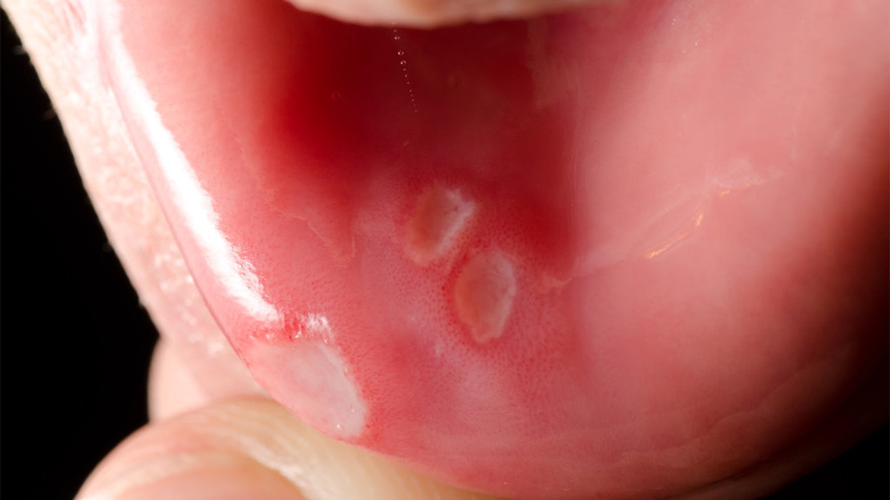

口腔溃疡 (口疮)

- 外观:通常是圆形或椭圆形的溃疡,中间有淡黄色或白色的假膜(坏死组织),周围有一圈红色的晕环,看起来就像一个“小坑”。

- 感觉:疼痛明显,尤其在进食、说话或刷牙时,通常在1-2周内可自行愈合。

- 原因:精神压力大、作息不规律、缺乏维生素(如B族)、食物刺激(如辛辣、过硬)、咬伤等。